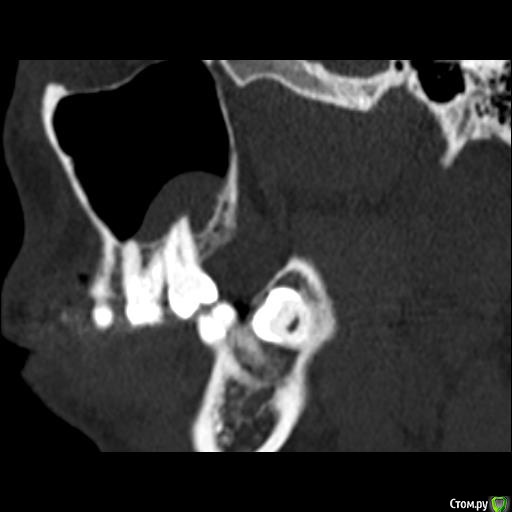

Юлия2386 Опубликовано 30 июля, 2020 Поделиться Опубликовано 30 июля, 2020 Добрый день, уважаемые врачи! Прошу вашей помощи, так как уже замучалась я конкретно. У меня уже 9 месяцев боли в правой стороне лица давящего характера. Давит на лоб, глаз, иногда висок. С декабря 2019 выявили фронтит-гайморит, проходила лечение у Лора и ещё невролога. Окончательного результата по выздоровлению за это время не достигнуто. Видимо это одномерный гайморит, так как постоянно какое-то воспаление формировалось у зубов 1.6;1.7;1.8. Многие стоматологи не видят проблем в зубе 1.6. Посоветовали удалить зуб 1.8 так как там был глубокий десневого карман. Удалила, а воспаление разрослось ещё больше (после удаления поцарапала щеку зубом 1.7, возможно из-за этого разрослось воспаление?!) После удаления прошёл месяц, а картина сейчас такая https://yadi.sk/d/ziceEN_jVZ9IkwВ итоге последний врач сказал, что все-таки проблема идёт от зуба 1.6, так как не запломбирован один канал, но из-за того что у зуба входят корни в гайморовых пазуху, лечить его не видет смысла, порекомендовал его удалить и через лунку вычиститься всю слизь, но он этим не занимается. Теперь я замешательстве и не знаю, что мне с этим делать, а самое ужасное, что глаз от этого болит( Уважаемые доктора, очень прошу вашей помощи, выскажите пожалуйста ваше мнение и может посоветуете к кому с этим можно обратиться в Москве. Ссылка на комментарий

wladdX Опубликовано 31 июля, 2020 Поделиться Опубликовано 31 июля, 2020 Представленная спиральная КТ не позволяет детально рассмотреть корневые каналы зубов и тп, чтобы получить какое-то внятное суждение.На уровне зубов 18, 17 и 16 есть локальное утолщение слизистой оболочки синуса и это всё, что из этого исследования можно выяснить. Адекватность обтурации корневых каналов зуба 16 оценить не представляется возможным (по крайней мере в моём понимании).Я бы порекомендовал сделать КЛКТ (конусно-лучевую компьютерную томографию), используемую в стоматологии. Ссылка на комментарий